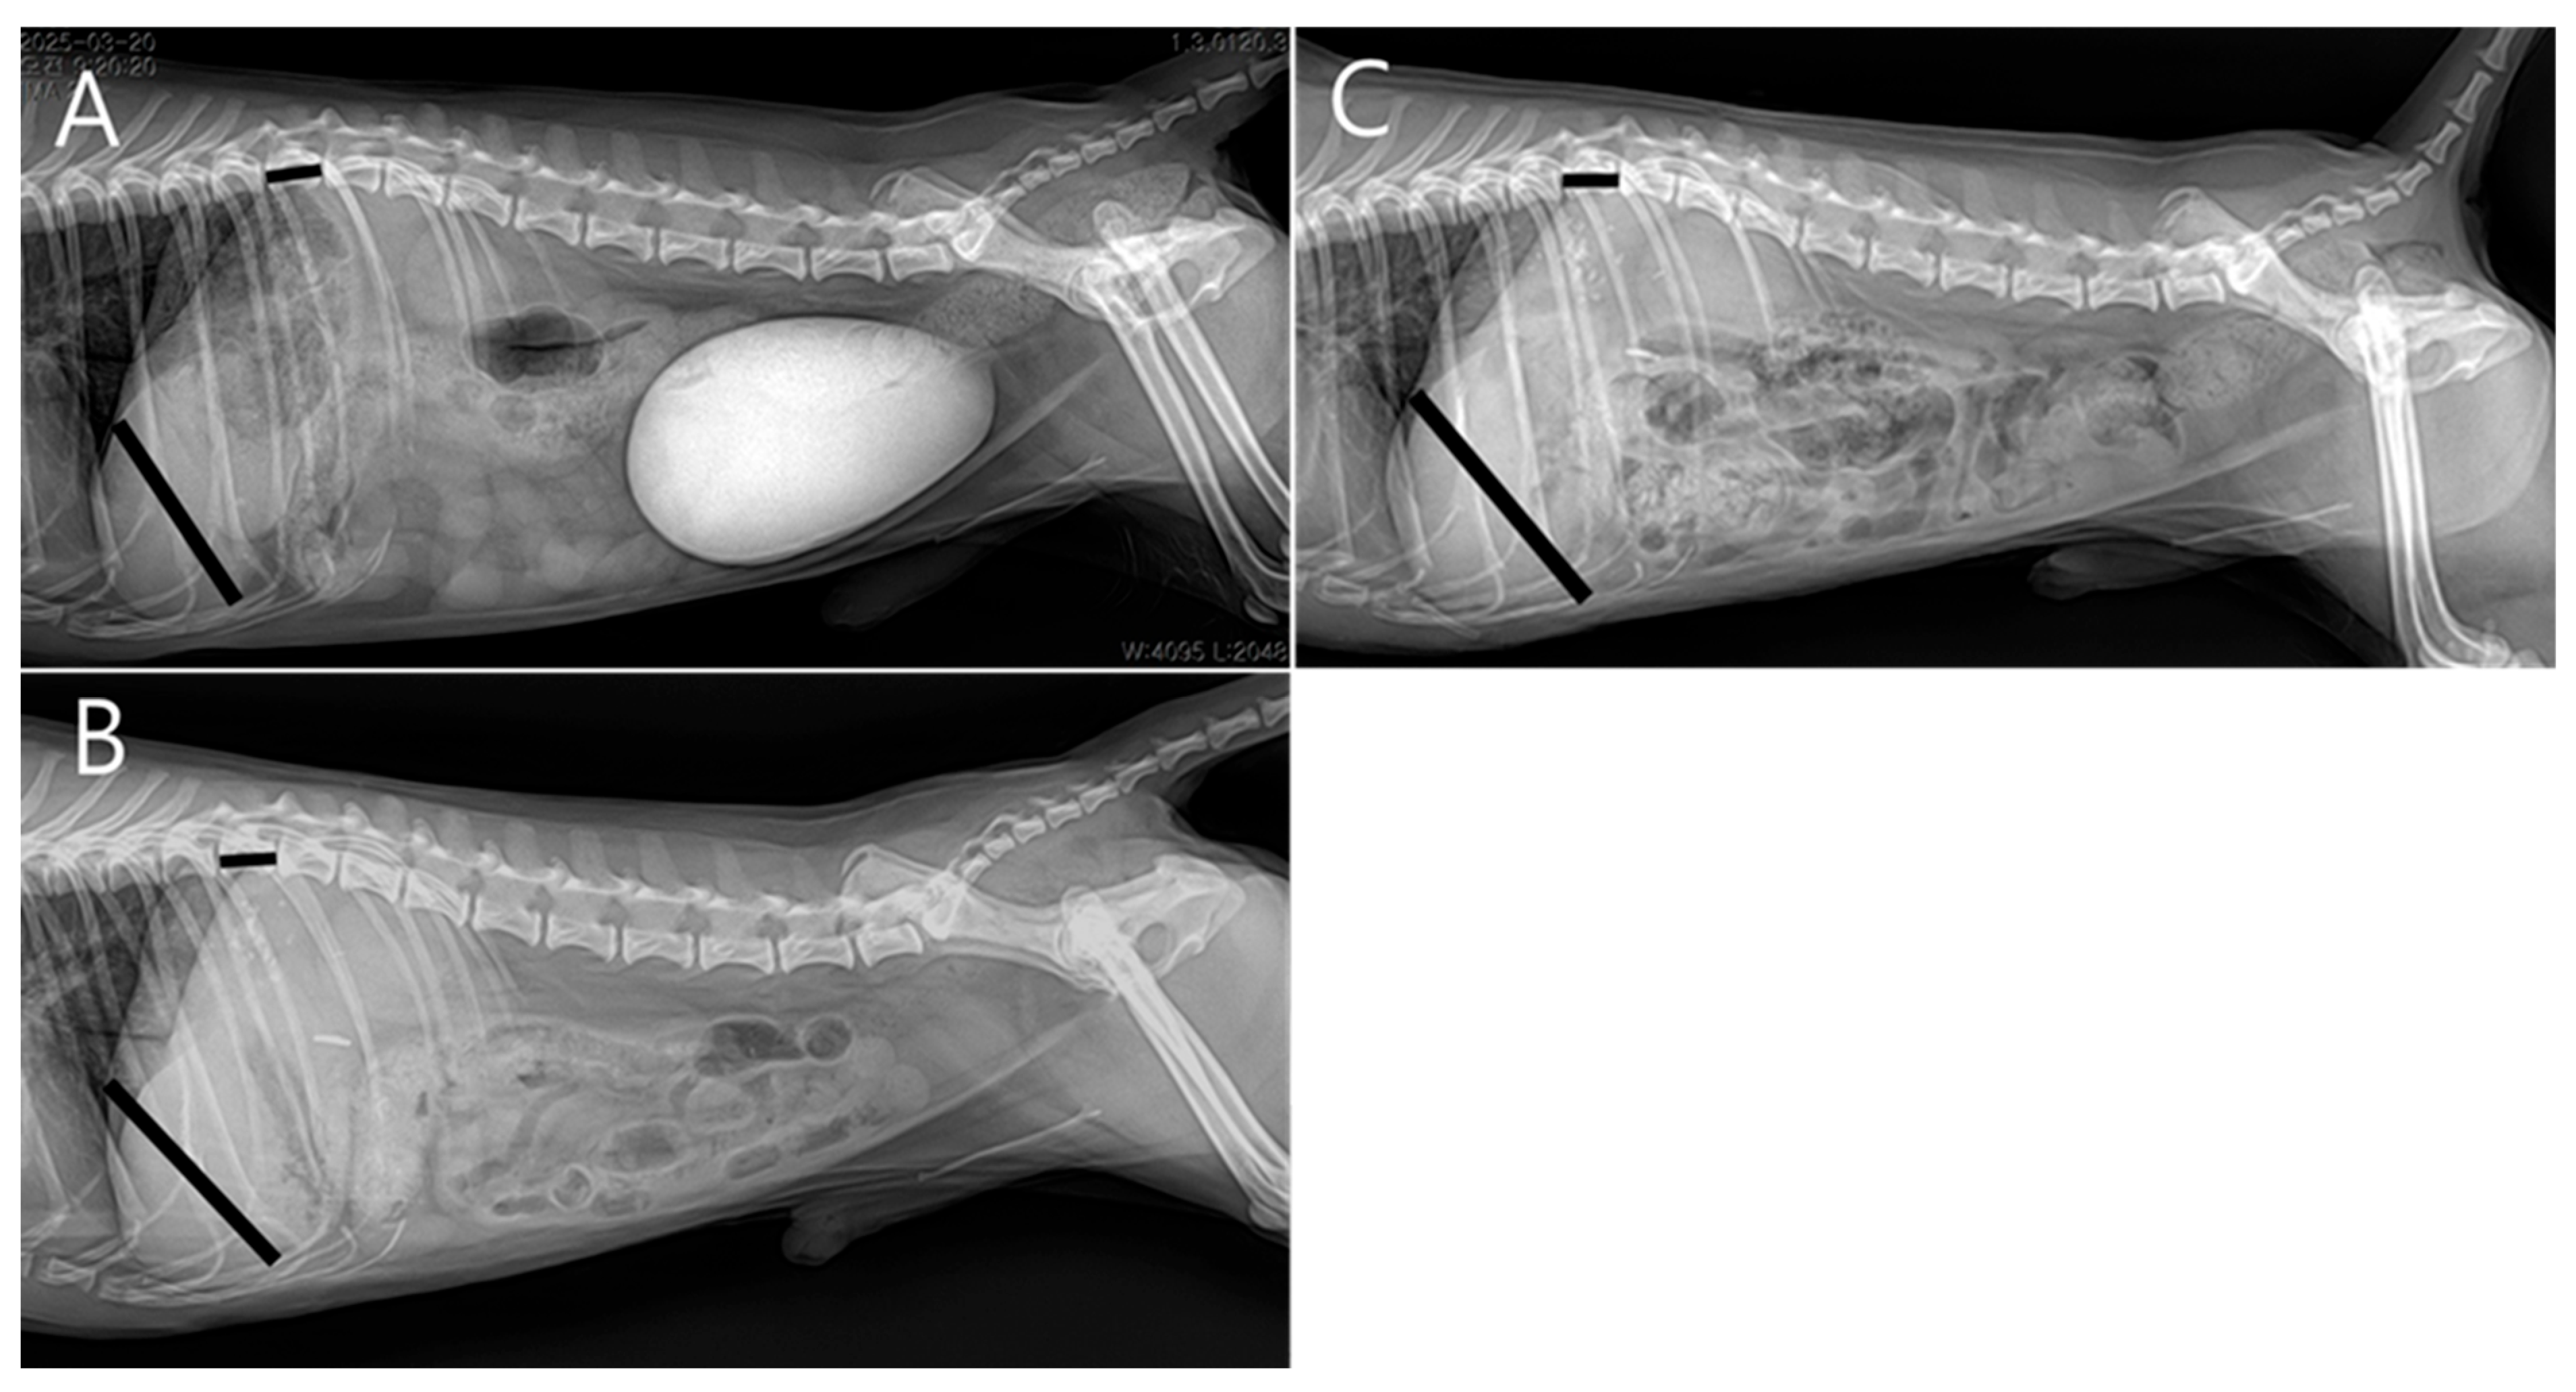

At the two-week postoperative follow-up, no surgical complications were noted. Subsequent rechecks were spaced at monthly intervals. Four months postoperatively, serum biochemistry showed normal hepatic enzyme levels, and radiographs demonstrated increased liver size compared to preoperative imaging (Figure 6). The patient was receiving levetiracetam (5–10 mg/kg PO BID), ursodeoxycholic acid (10 mg/kg PO BID), and silymarin (10 mg/kg PO BID), with plans for gradual tapering.

Figure 6.

Radiographic liver size evaluation using the liver-to-T11 vertebral length ratio (right lateral view). Measurements were taken from the ventral border of the caudal vena cava to the caudoventral liver apex (liver length), and the midpoint of T11 (vertebral length). Black lines indicate the measured liver length and the T11 vertebral length used to calculate the liver-to-T11 ratio. (A) Preoperative ratio: 4.13. (B) One month postoperatively: 4.52. (C) Four months postoperatively: 4.90, suggesting progressive hepatic enlargement following extrahepatic portosystemic shunt (EHPSS) attenuation.